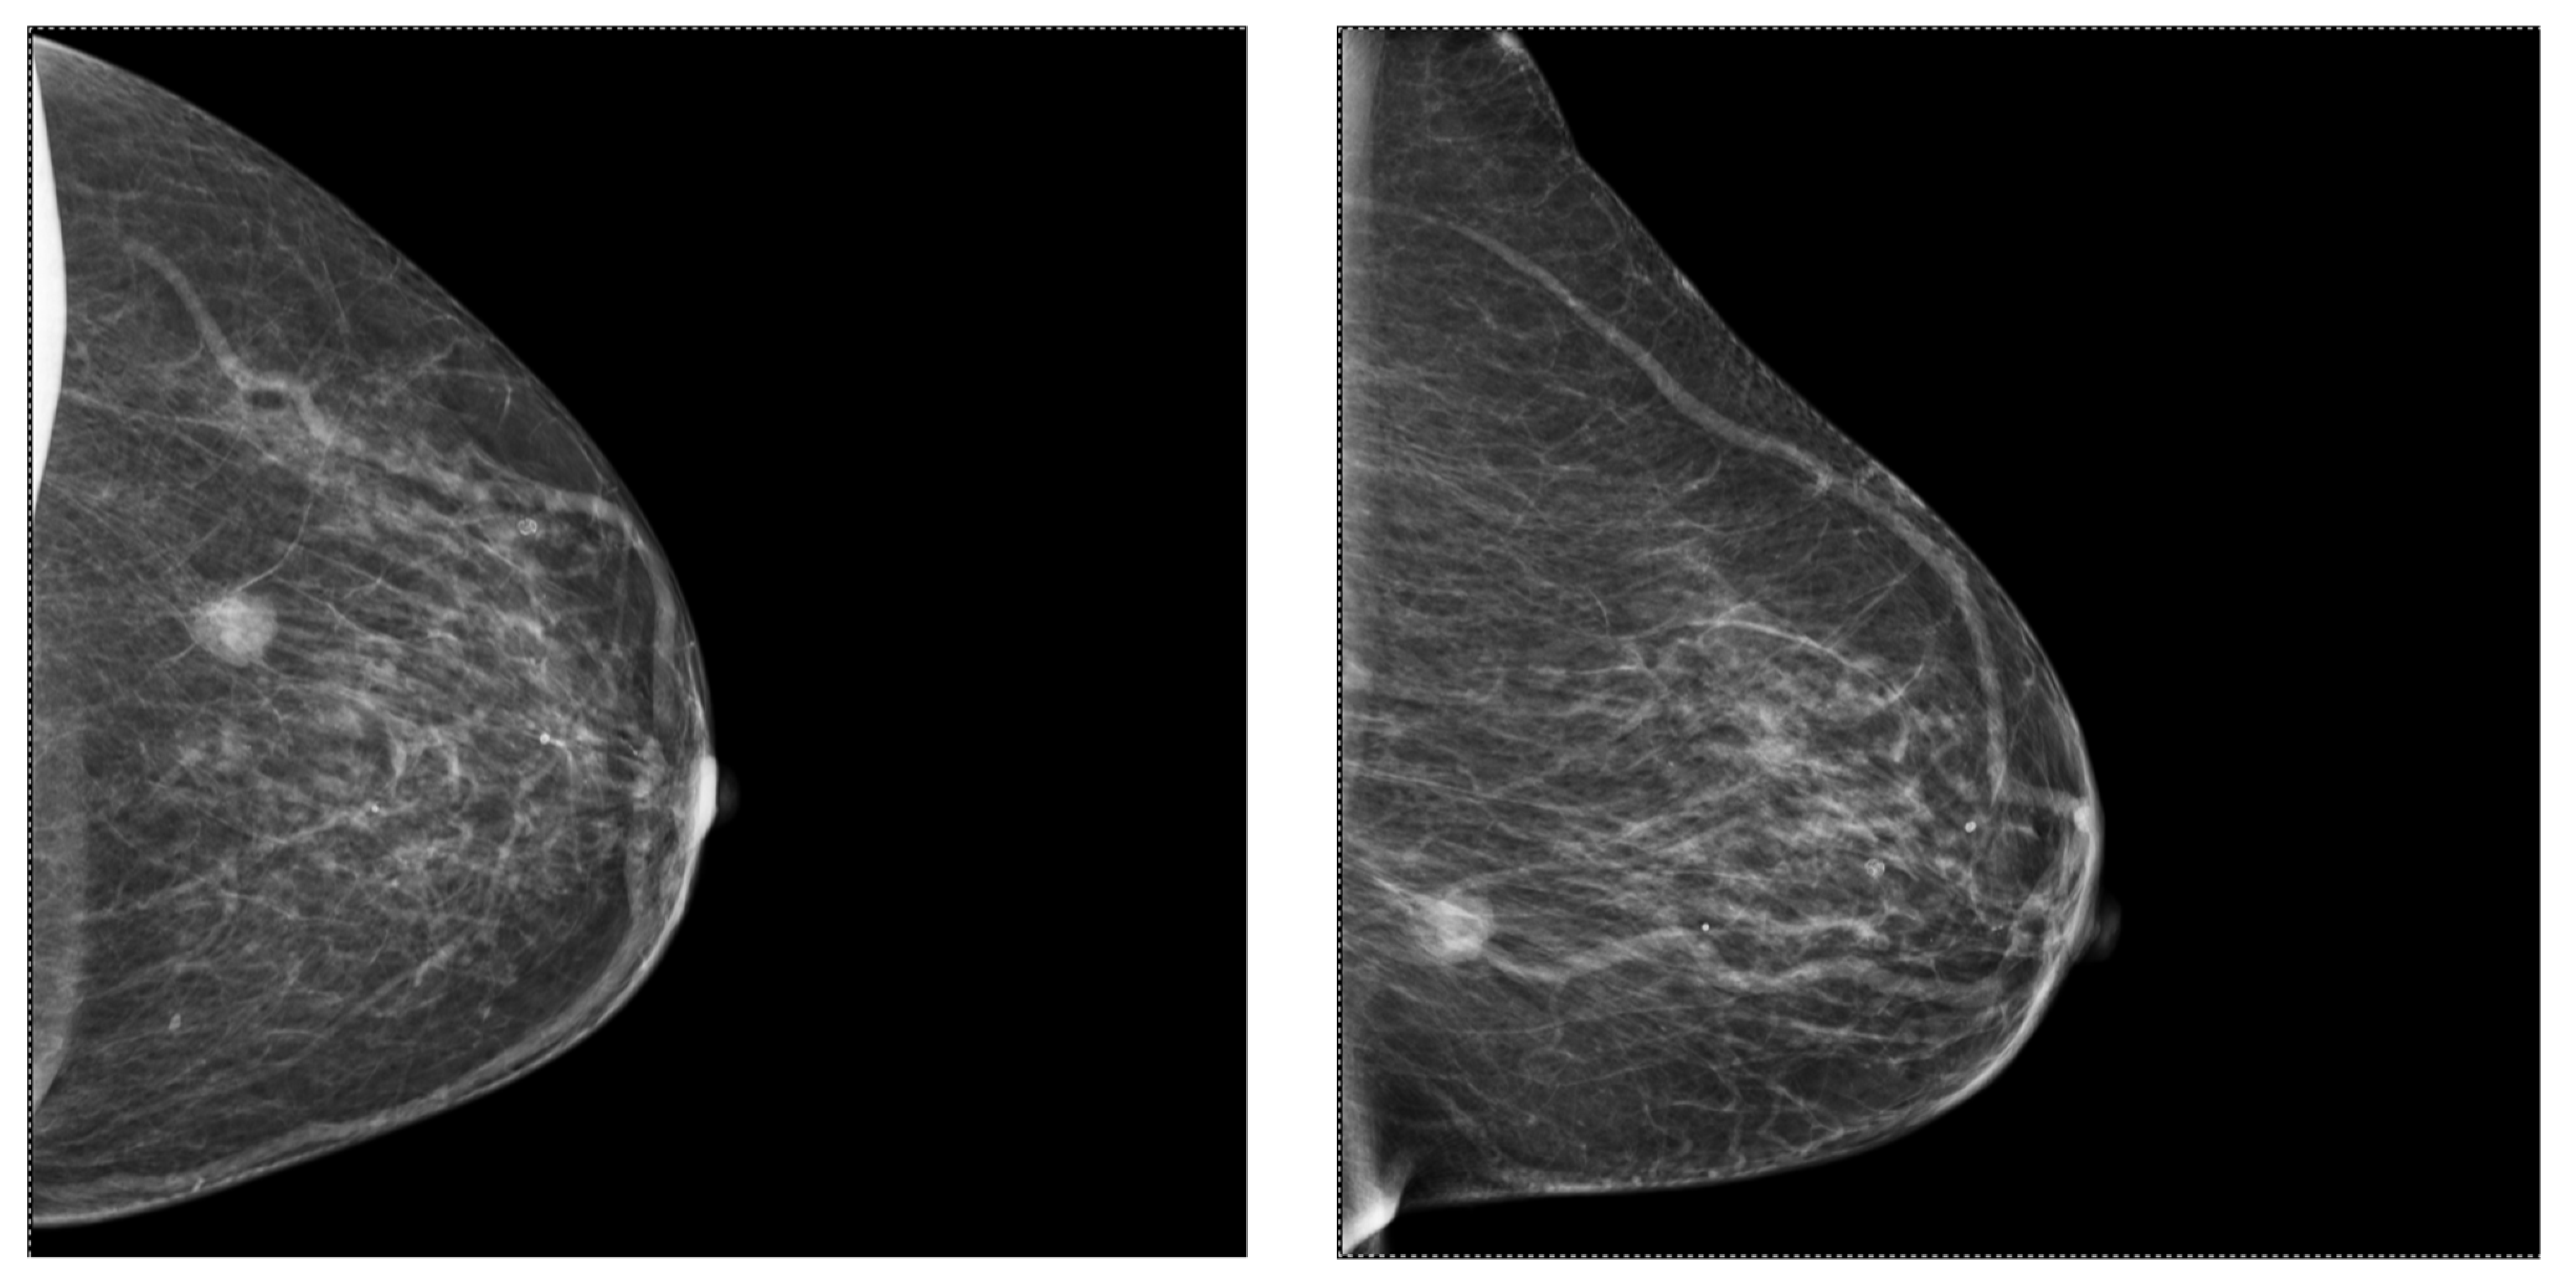

2.2. Mammography (MG)

3.5. Correlations between Molecular Subtypes of BC and Their Mammographic Features

3.6. Correlations between Molecular Subtypes of BC and Their Ultrasonographic Features

- Shaikh, S.; Rasheed, A. Predicting Molecular Subtypes of Breast Cancer with Mammography and Ultrasound Findings: Introduction of Sono-Mammometry Score. Radiol. Res. Pract. 2021, 2021, 6691958. [Google Scholar] [CrossRef] [PubMed]

- Li, N.; Gong, W.; Xie, Y.; Sheng, L. Correlation between the CEM imaging characteristics and different molecular subtypes of breast cancer. Breast 2023, 72, 103595. [Google Scholar] [CrossRef]

- Ian, T.W.M.; Tan, E.Y.; Chotai, N. Role of mammogram and ultrasound imaging in predicting breast cancer subtypes in screening and symptomatic patients. World J. Clin. Oncol. 2021, 12, 808–822. [Google Scholar] [CrossRef]